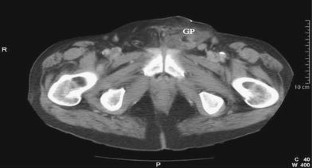

Unusual presentation of acute pancreatitis: an irreducible inguinoscrotal swelling mimicking a strangulated hernia

We report an unusual presentation of acute pancreatitis as a tender, irreducible, inguinoscrotal swelling mimicking a strangulated hernia. Lack of abdominal symptoms or signs can lead to misdiagnosis and unnecessary surgery.

Fig. 3.